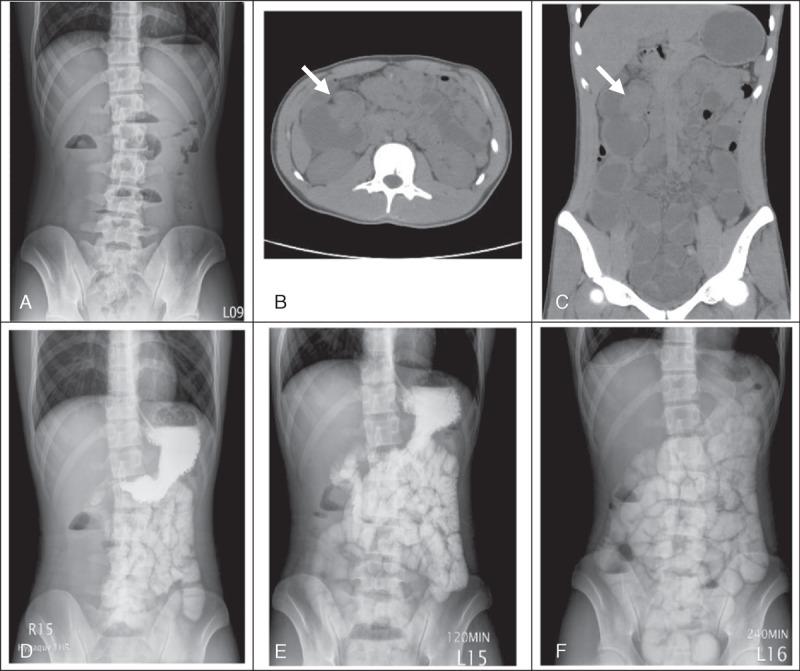

Colon carcinoma is a rare disease in the pediatric population. Here is a report on a 17-year-old male adolescent with colon adenocarcinoma who presented with recurrent epigastric colic pain for 1 month. Diagnostic laparoscopic surgery revealed a 3.2 × 3 cm tumor at the ascending colon, with serosal involvement and peritoneal metastasis. Clinical differences of colorectal carcinoma among children and adults are reviewed and summarized.

结肠癌在儿童群体中是一种罕见疾病。本文报道了一名17岁男性青少年,患有结肠腺癌,出现反复上腹部绞痛1个月。诊断性腹腔镜手术显示升结肠有一个3.2×3厘米的肿瘤,伴有浆膜受累和腹膜转移。对儿童和成人结直肠癌的临床差异进行了回顾和总结。